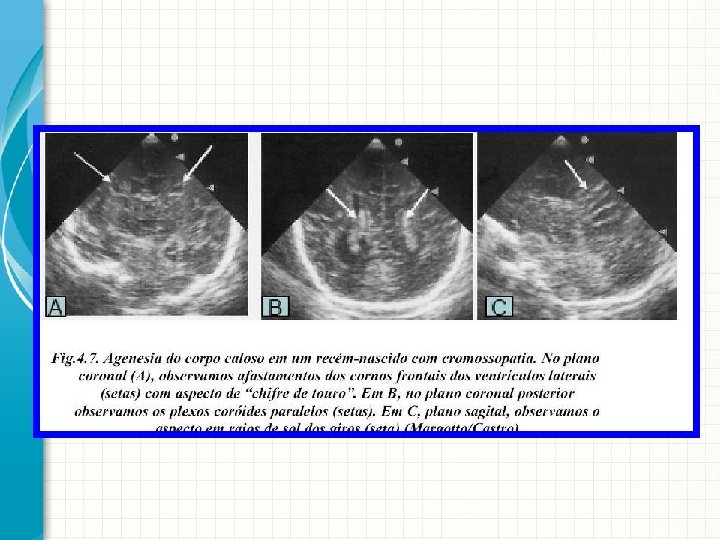

Agenesia de corpo caloso Neurossonografia Neonatal (Capítulo IV): Principais Malformações Cerebrais Autor(es): Paulo R. Margotto

AGENESIA DE CORPO CALOSO • Incidência: 1, 8 /10. 000 nascidos vivos. • Classificação: Completa: Embriogênese defeituosa. Parcial: malformação verdadeira. - Anterior: encefalomalácia frontal - Posterior: desenvolvimento incompleto.

AGENESIA DE CORPO CALOSO • Fatores de Risco: - Prematuridade: > 4 x - Mãe >= 40 anos: > 6 x - Associações: - Distúrbios do desenvolvimento generalizados. - Erro inato do metabolismo. • - Cromossomopatias: Anomalias no cariótipo podem ser encontradas em 20% (a Trissomia do 18 foi relatada ocorrer em 30%, a trissomia do 8 e do 13 em 20% cada). Postula-se que os cromossomos 8, 13 e 18 influenciam diretamente o desenvolvimento do corpo caloso.

AGENESIA DE CORPO CALOSO • Diagnóstico: USTV • USTV Normal: banda sonolucente no plano sagital. • USTV ACC: distorção da arquitetura craniana, aumento dos ventrículos laterais, cornos frontais do 3º Ventrículo mais separados (aspecto de “chifre de touro”), distorção do trajeto da artéria calosa anterior.

AGENESIA DE CORPO CALOSO